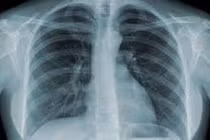

(khoahocdoisong.vn) - Bệnh phổi có nhiều loại như viêm phổi, hen phế quản, tràn khí màng phổi, lao… Biết cách chế biến các món ăn – bài thuốc sẽ giúp hỗ trợ điều trị bệnh rất tốt.